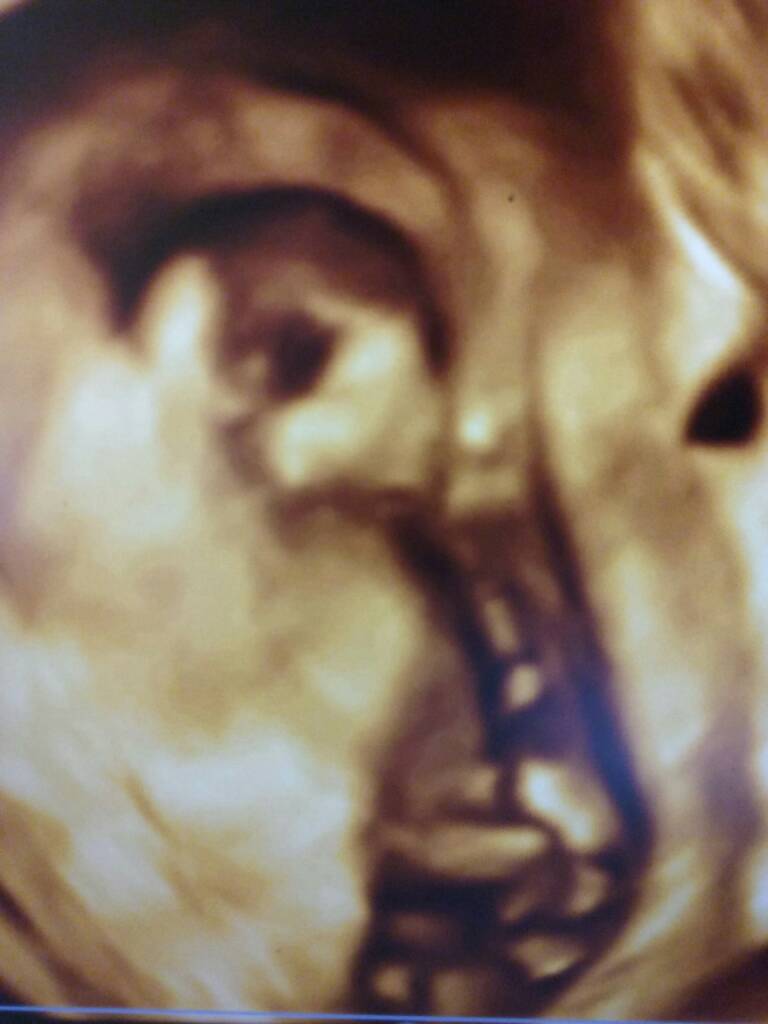

Hej ja już po usg, dzidzia ma 6,63 cm czynność serca 157/min. Rozwija się prawidlowo, żołądek i pęcherz widoczne. Dzidzia tak jest ułożona że lekarz aby ja pomierzyć musial mi robić usg dowcipnie i przez brzuch [emoji6]

Hej ja już po usg, dzidzia ma 6,63 cm czynność serca 157/min. Rozwija się prawidlowo, żołądek i pęcherz widoczne. Dzidzia tak jest ułożona że lekarz aby ja powierzyć musial mi robić usg dowcipnie i przez brzuch [emoji6]